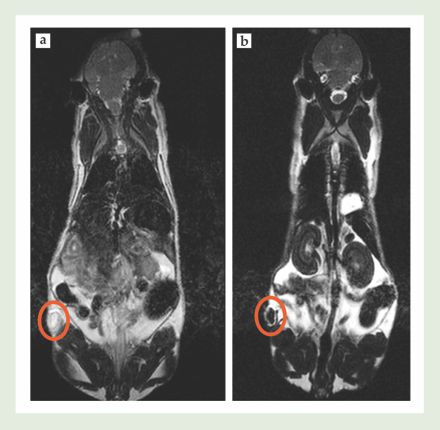

Nanoparticles do in fact selectively accumulate in tumor tissue via a purely physical phenomenon called the enhanced permeability and retention (EPR) effect. 3 Figure 2 tracks a small molecular (non-nanoparticle) contrast agent over 45 minutes as it penetrates a tumor implanted in the flank of a mouse. By the time the molecule starts to reach the tumor core, it’s already being cleared from parts of the tumor periphery. In contrast, figure 3 shows a different mouse injected with iron oxide nanoparticles. The entire tumor becomes progressively darker with time, which indicates nanoparticle accumulation via the EPR effect. The nanoparticle concentration in the tumor was still increasing after 24 hours.

Figure 3. Iron oxide nanoparticles were injected into a mouse implanted with a colon cancer tumor (circled in orange). (a) Before injection, the tumor appeared bright in a magnetic resonance image. (b) Twenty-four hours after injection, accumulation of nanoparticles caused the tumor to appear dark. In fact, the contrast in the tumor was still increasing after 24 hours. (Courtesy of Marcelino Bernardo and Lilia Ileva.)